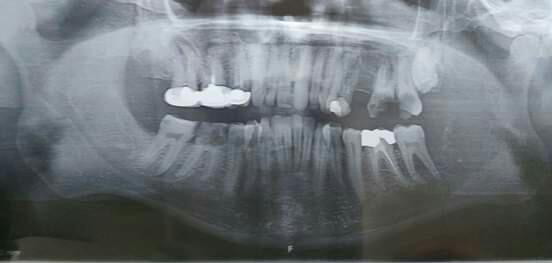

"أحسست بكسرٍ في طاحونتي أثناء قضمي لحبة فستق، لم أُولِ اهتماماً كبيراً في حينها إلا أن انتفاخاً بدأ بالظهور على الشق الأيسر من وجهي ساقني لمراجعة الطبيب".. لتبدأ رحلة الكشف عن السبب، أجرى مهند عدة صورٍ إشعاعية على مدى ثلاثة أسابيع قبل أن يتلقى تحويلاً إلى مدينة رام الله من أجل إجراء صورة طبقية، تلاها فحص بواسطة الخزعة، ليتبين وجود ورم حميد.

Squamous cell Carcinoma سرطان في الفك

لم يتوقع مهند أن يكون الإجراء الذي تلا التشخيص النهائي مؤلماً وصعباً إلى ذلك الحد؛ عملية جراحية يتم فيها إزالة نصف الفك السفلي من جهة اليسار.. العظام، قاعدة اللسان حتى الشفة الضاحكة، أي أنه سيدخل لإجراء عملية ستستمر لعشر ساعات لن يخرج منها كما كان أبداً، بل وستبدأ من بعدها سلسلة طويلة من جلسات العلاج الكيماوي والنووي.. انتهت العملية تاركةً خلفها قطع البلاتين المزروعة في فكه، وخرطوماً في معدته من أجل التغذية..